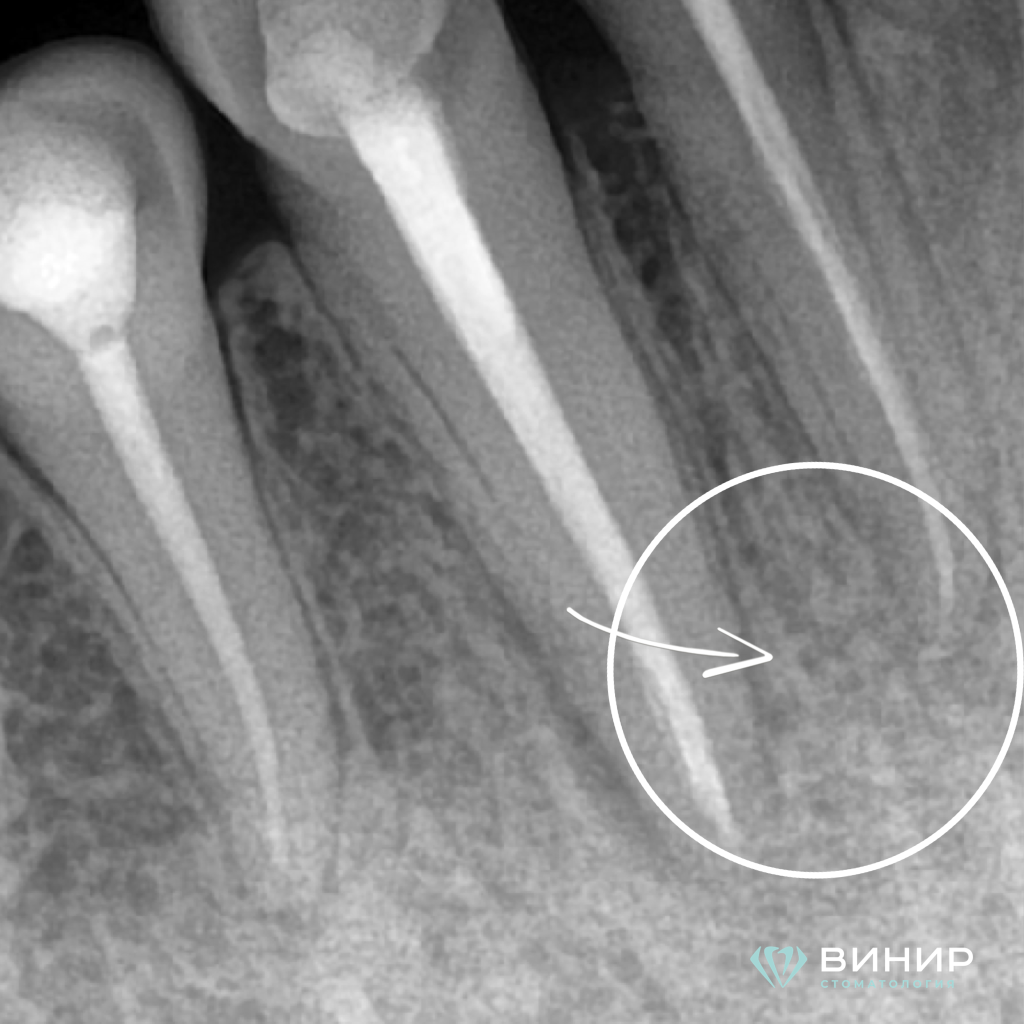

Пациент обратился в клинику с жалобами на боль в зубе на нижней челюсти. При помощи современных методов диагностики был выявлен очаг в области 4.2 зуба, что подтверждено рентгенологически.

1. Очаг деструкции

1 пункт.PNG